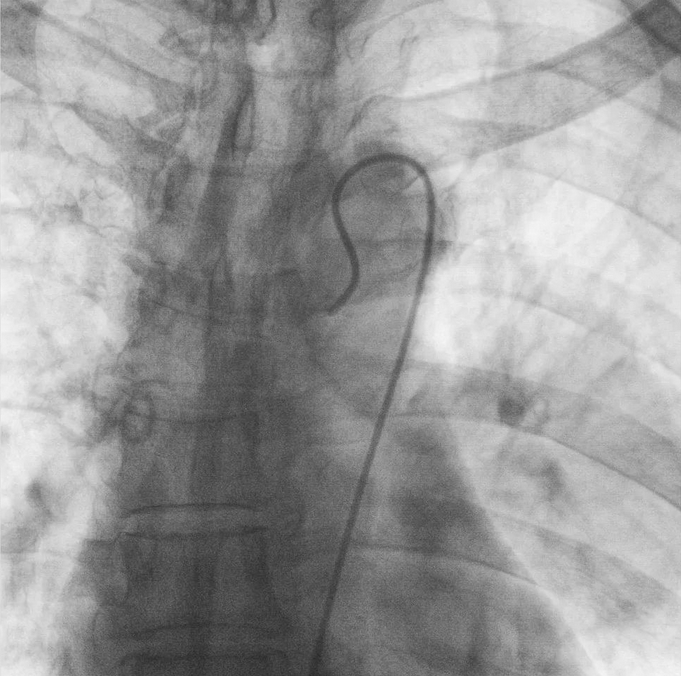

支氣管動脈栓塞+化療灌注術(shù)

在普愛醫(yī)療移動式平板介入中C影像的引導(dǎo)下,醫(yī)生為患者實(shí)施雙側(cè)支氣管動脈栓塞+化療灌注術(shù)。

在微導(dǎo)絲的配合下,先后分別超選擇①至3支左側(cè)支氣管動脈腫瘤供血動脈,經(jīng)微導(dǎo)管推注栓塞微粒球栓塞腫瘤動脈。栓塞結(jié)束后,再次用移動式平板介入中C做造影檢查,見腫瘤染色消失。